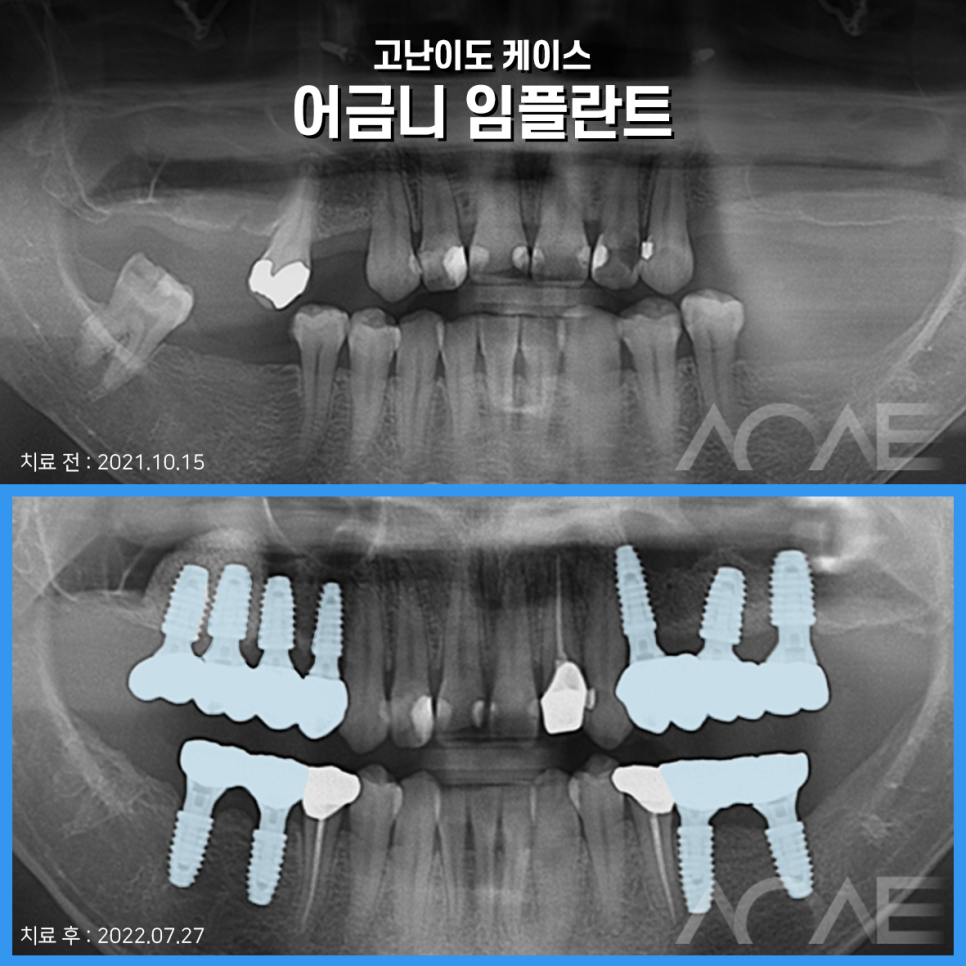

아래는 저희 치료 증례인데요

한 번 읽어봐주세요 ^^